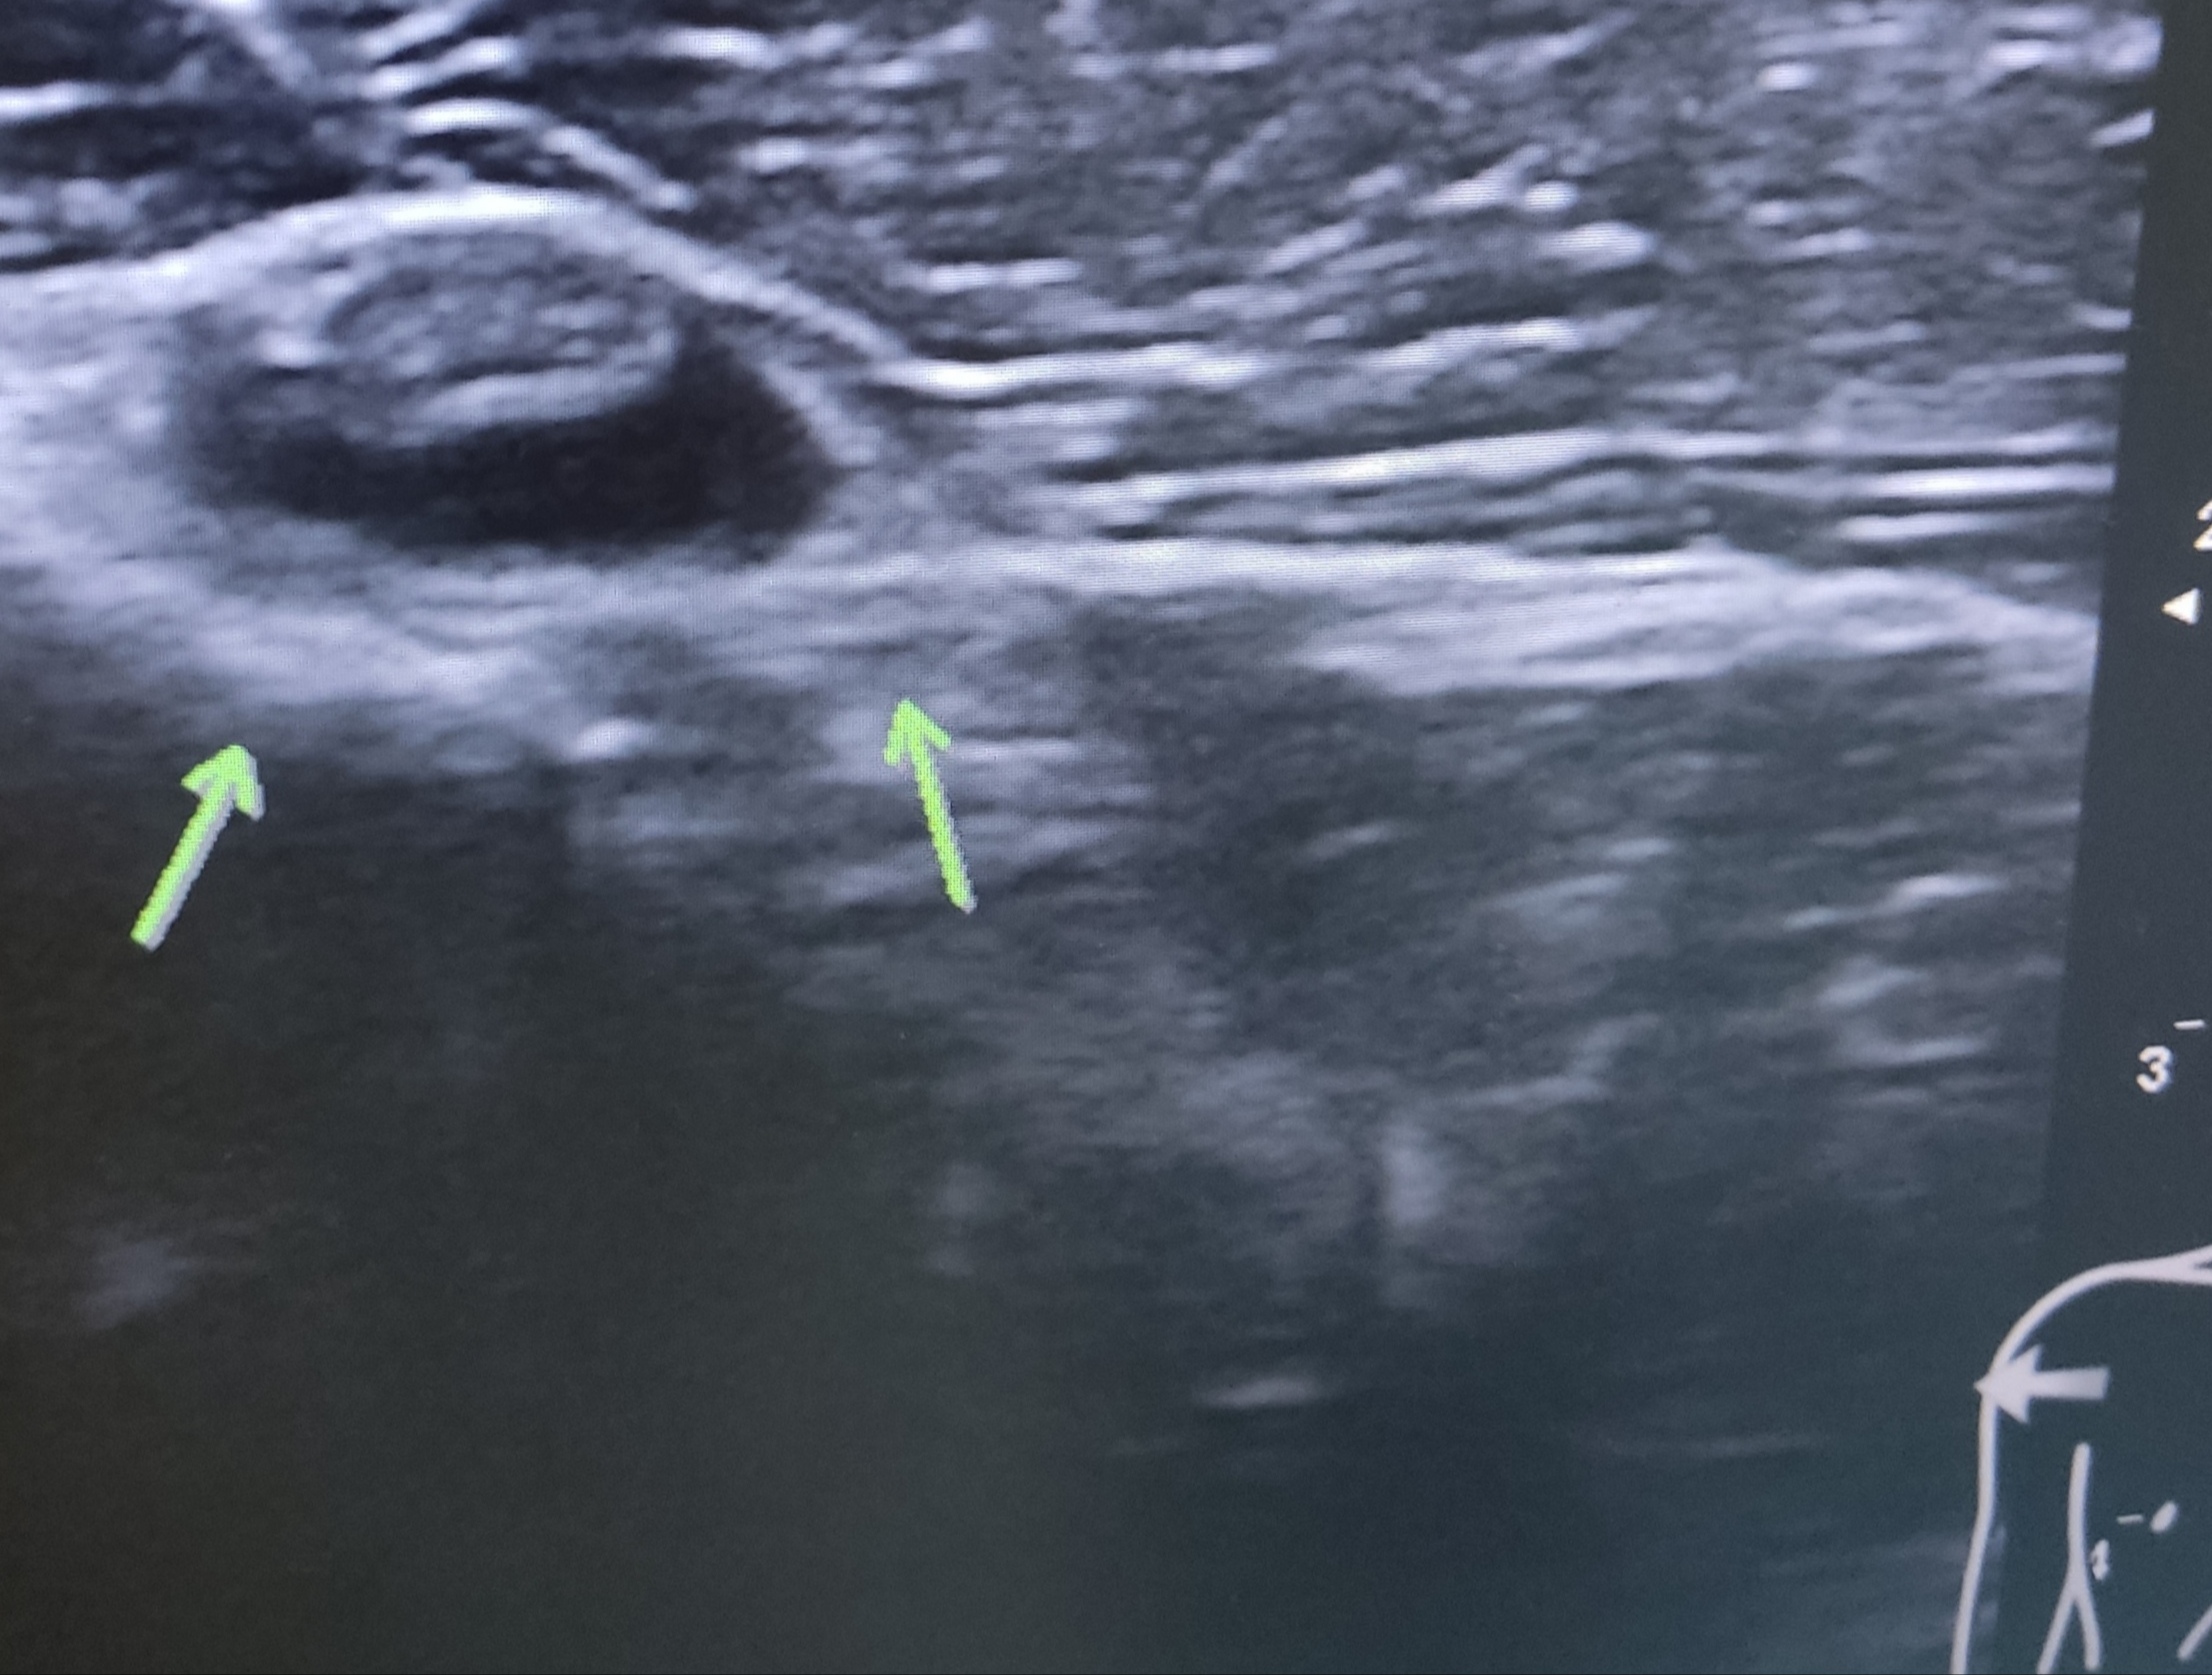

El tendón del bíceps conserva su morfología y ecoestructura homogénea y fibrilar, lo que apunta a que ese líquido sea un derrame bicipital.

En el corte transversal del supraespinoso se observan varias imágenes hipoecoicas bien delimitadas en el espesor del tendón que podrían hacer sospechar una rotura parcial intrasustancia.

En el corte transversal del supraespinoso se observan varias imágenes hipoecoicas bien delimitadas en el espesor del tendón que podrían hacer sospechar una rotura parcial intrasustancia o podrían corresponder con una persistencia de fibras musculares del supraespinoso más allá del arco óseo acromial (lo que puede ser bastante frecuente en gente joven menor de 50 años). Podemos "tirarnos a la piscina" y sugerir que tiene un supraespinoso que distalmente al acromión/ligamento coracoacromial está formado por fibras tendinosas en su mayoría, acompañadas por zonas de fibras musculares que con el envejecimiento se irán fibrosando, convirtiéndose en fibras tendinosas.